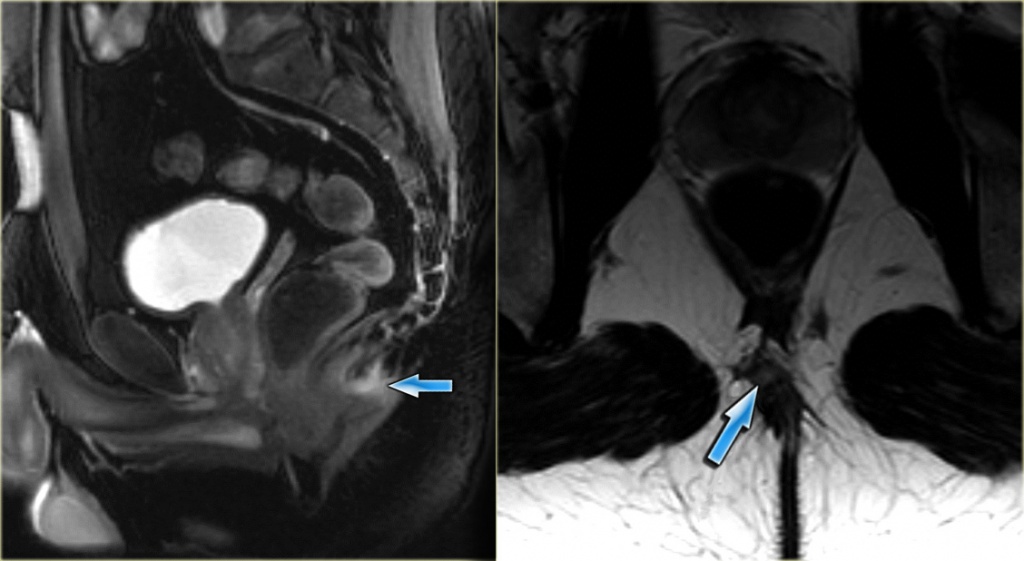

Довольно редко встречающийся клинический случай, когда в копчиковой области между ягодиц располагается узкий канал, стенки которого выстланы эпителием, с одним или несколькими точечными отверстиями внутри которых могут быть волосяные фолликулы и сальные железы. Поэтому в народе называют пилонидальным синусом (с лат."волосяное гнездо").